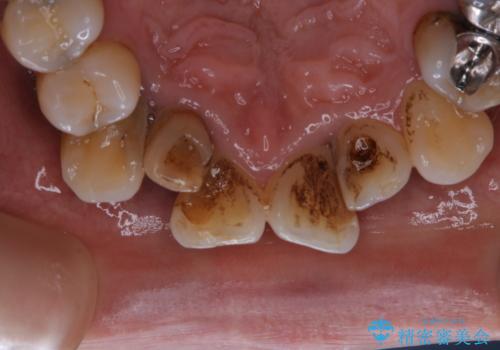

全体的な治療の開始前に着色取り